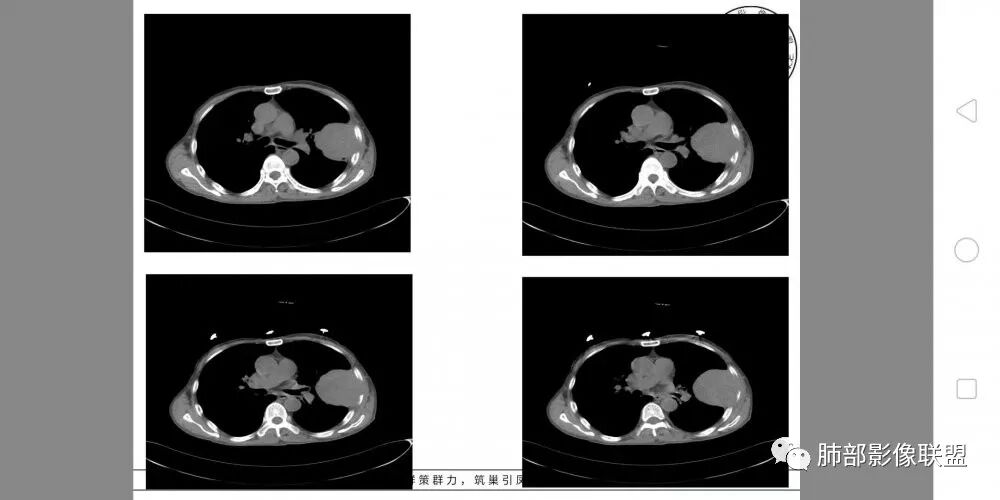

老年男性,外伤入院,“左上肺”实性肿块,边缘光滑,突破壁层胸膜并侵犯肋骨及肋间肌,增强扫描轻度强化,可见明显坏死。

左肺上叶实性肿物,左肺上叶支气管受压变窄,病灶边缘光滑,轻度分叶,病灶轻度强化内部可见多发小灶坏死,坏死边界模糊,病灶突破壁层胸膜侵及左侧部分肋骨及肋间肌,考虑恶性,肉瘤样癌,鉴别诊断低分化腺癌。

• 胸CT:左肺上叶实性占位,病灶与支气管无关,病灶对斜裂挤压,病灶周围光滑,未见分叶、毛刺;纵隔窗可见病灶内低密度区,病灶对胸壁侵袭,并可见肋骨破坏。

患者中老年男性,外伤后入院。胸部CT:左肺上叶实性肿块,近心侧边界清楚,边缘光滑,胸壁侧突破壁层胸膜、肋间隙并侵犯肋骨及肋间肌,增强扫描轻度强化,可见近心侧多发片状坏死,未见明显淋巴结肿大。综合考虑SFT,鉴别肉瘤及结核。

胸CT:左上肺实性大肿块,边缘光滑,突破胸膜侵犯肋骨及肋间肌,纵隔淋巴结肿大,增强呈轻度强化,可见明显片状坏死。

胸部CT所见左肺上叶尖后段胸膜下较大山丘形肿块,边界清楚,宽基底与胸膜相贴,边缘与胸膜呈直角及锐角相交。邻近上叶尖后段支气管受压推挤,叶裂局部膨隆,病灶周围见少许磨玻璃密度影,边界不清。纵膈窗显示,肿块密度均匀,增强扫描呈不均匀轻度强化,邻近肋骨骨质破坏,病变沿肋间隙向外侵犯,局部胸膜增厚。纵膈内见多发小淋巴结,未见胸腔积液征象。综合考虑恶性占位,肉瘤样癌可能性大。腰椎及髋部考虑骨转移。